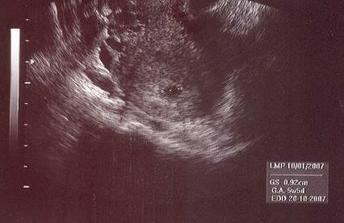

Na svet by som mala prísť 17.10.2007, budem sa volať Emka (v prípade, že sa pani doktorka pomýlila, tak Palinko) a maminka s tatinkom sa na mňa stráááášne tešia!